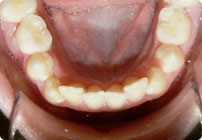

Antes

Caso: 11 años

Adolescente: Clase II

Mordida Cruzada Posterior

Sin extracción

Sin uso de expansores

6 alambres superiores

5 alambres inferiores

Sin uso de elásticos

Retenedores: Interior Fijo de TMA y Hawley en superior

Tiempo de tratamiento: 14 Visitas